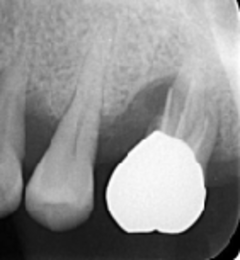

歯周病が進行し、グラグラして物が嚙めず、抜歯してインプラントにしていくことに。

インプラントはストローマンを使用、上部構造はジルコニアセラミックス